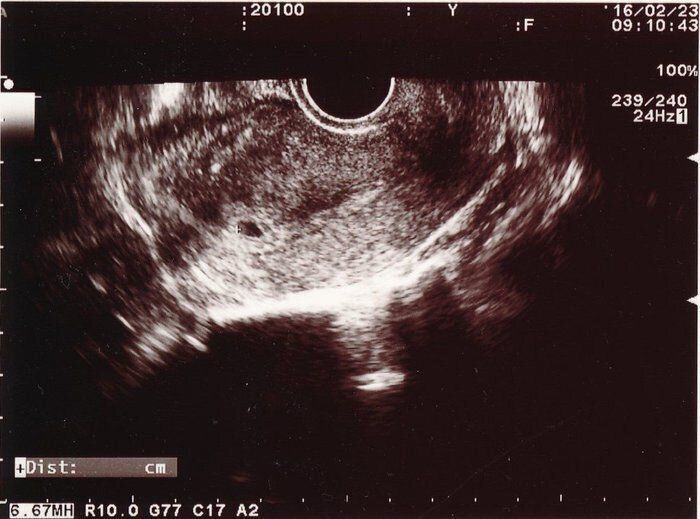

Tomomiさんの妊娠5週目のエコー写真 胎嚢が確認できました

妊活を始めて3年。稽留流産の緊急手術から9カ月後、ついに娘の1枚目のエコー写真をもらいました。新たな土地に引っ越し、右も左も分からない中で1番初めに調べた病院は、レディースクリニックの情報でした。

先生との相性が良かったのか、通い始めて半年で妊娠、クリニック卒業になるなんて思いもせず、飛び上がって喜びました。